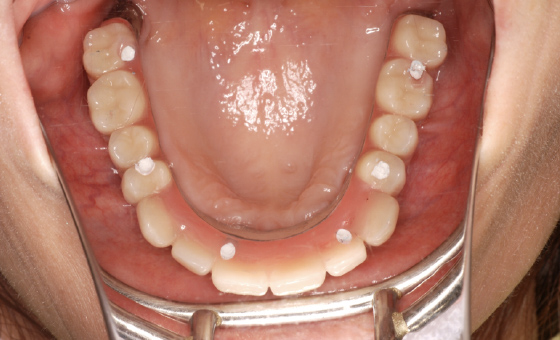

当院では手術当日に固定式の仮の歯を装着します。その後、半年間その仮歯で日常生活を送っていただき、経過をみていきます。インプラントと骨がしっかりと固定されたら、最終的な人工歯を入れていきます。

この患者様の場合、治療後半年後のレントゲン写真を見ると、骨とインプラントがしっかりと結合している様子が確認できたので、最終的な人工歯を装着しました。

人工歯はネジでインプラントに固定してありますので、万が一破損などの場合でも、専用のドライバーで外して修理が可能です。